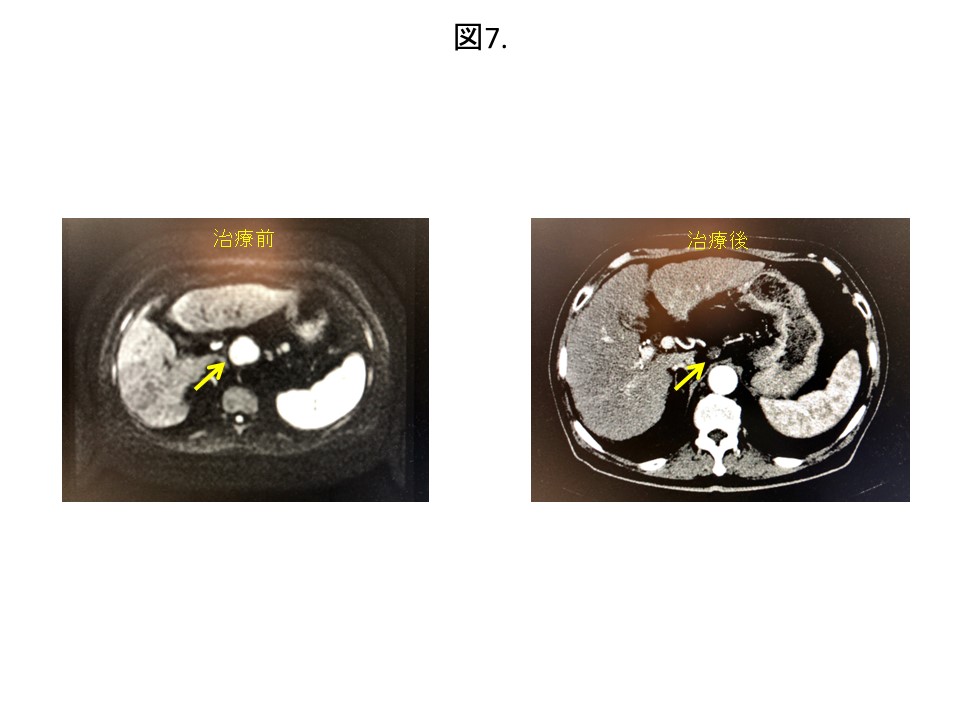

●肝細胞癌65歳男性:肝細胞癌治療後の患者さんです。腹腔内のリンパ節に再発認めました。通常、リンパ節再発のような遠隔転移の場合は、例えその数が1つであっても標準治療は抗癌剤投与となります。しかしながら、この患者さんは心臓の病気と維持透析をされている関係で、まずはサイバーナイフ治療を行うこととしました。幸いなことに治療後、リンパ節転移は消失して(図7)、その後5年以上再発を認めていません。